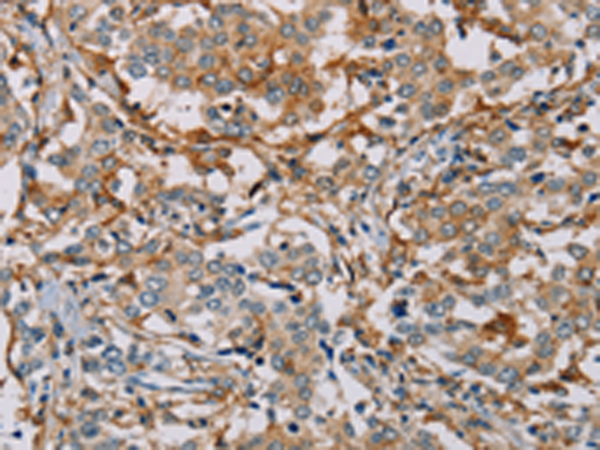

分类: 科研抗体货号: P08511别名: NYD-sp9应用: IHC反应种属: Human, Mouse, Rat